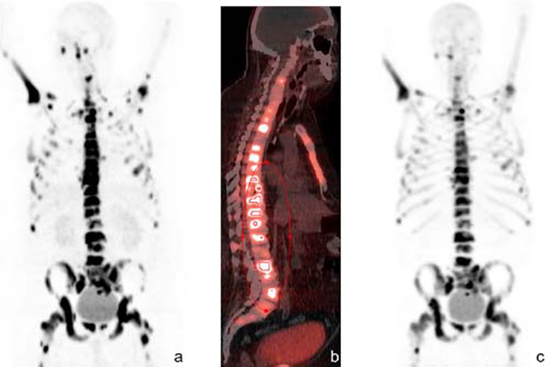

Somatostatin receptor imaging

The expression of SSTRs has been found in neuroendocrine tumours, small cell lung cancer, renal cell carcinoma, malignant lymphoma, breast cancer, and prostate cancer. PET-CT using somatostatin ligand analogues labelled with 68Ga has become a new golden standard in imaging of NETs with specificity and sensitivity well above 90% and advantages over conventional radiologic and scintigraphic imaging [14, 146-149]. It is the most pronounced example of theranostics [6, 7, 150].

The feasibility of quantitation of SSTR density has been demonstrated both preclinically [25, 160] and clinically [24] using [68Ga]Ga-DOTA-TOC. Although a ten-fold higher affinity for the SSTR2 had been demonstrated for DOTA-TATE as compared to DOTA-TOC in vitro in transfected cell cultures [161], no statistically significant difference between [68Ga]Ga-DOTA-TOC and [68Ga]Ga-DOTA-TATE uptake could be observed in vitro in monkey brain tissue sections or in vivo in rat organs expressing SSTRs ( pituitary, adrenal, pancreas) [103]. Moreover, clinical study involving 40 patients did not verify the 10-fold higher affinity for the SSTR2 of [68Ga]Ga-DOTA-TATE, on the contrary, standardized uptake value (SUVmax) of [68Ga]Ga-DOTA-TOC tented to be higher [162]. Another aspect investigated preclinically is the influence of treatment with octreotide and interferon-a (IFNa) used for biotherapy of NETs on the uptake of [68Ga]Ga-DOTA-TATE. The exposure of the animals to the cold octreotide did not enhance the uptake of the tracer while IFNa did, however the mechanism of the observation was not clear [163, 164]. Gene therapy protocols were optimized on the basis of in vivo imaging ([68Ga]Ga-DOTA-TATE) of gene expression and quantitative monitoring of gene transfer [165].

[68Ga]Ga-DOTA-TOC (27), [68Ga]Ga-DOTA-TATE (28) and [68Ga]Ga-DOTA-NOC (29) (Figure 6) are the most commonly used analogues in clinical studies [2, 166, 167]. Their pharmacokinetics, blood clearance and target localization rate are compatible with half-life of 68Ga. Renal excretion, short scanning time, high sensitivity and resolution assure high contrast and quality images over organs of interest as well as accurate quantitation. Relatively low radiation dose is one more advantage that should be mentioned. They served for diagnosis, staging, prognosis, therapy selection and response monitoring of NETs and other types of cancers and diseases. [68Ga]Ga-DOTA-TATE was compared with [68Ga]Ga-DOTA-NOC in 20 patients in terms of detection rate and SUVs [168]. The agents had comparable diagnostic accuracy with higher SUVmax for the former. One more analogue, [68Ga]Ga-DOTA-2-Nal, Tyr3, ThrNH28-octreotide (DOTA-lanreotide, DOTA-LAN) was successfully used for lung and thyroid tumour detection [169].

The individualized diagnosis has been practiced in the selection of patients for PRRT, target definition for fractionated stereotactic radiotherapy (FSRT) planning, target volume delineation for intensity modulated radiotherapy [170-174]. The diagnosis on the cellular and molecular level and determination of the disease associated biomarkers provides basis for the treatment optimization and efficacy for a particular patient [175]. The personalized therapy planning necessity was demonstrated in retrospective study of ten patients examined with [68Ga]Ga-DOTA-TATE [176]. It was concluded that the radiotherapeutical dose should be determined by the tumour burden since the latter influences the radioactivity distribution to the healthy organs, and in particular the higher burden decreases the radiation accumulation in the kidney. The starting point of PRRT after preceding cold octreotide therapy in patients with NETs could be determined [177]. These imaging agents improved the detection rate and diagnostic accuracy [178, 179]. They were used for therapy planning and monitoring response to treatment [180], as well as influenced and changed the therapeutic course [181-184].